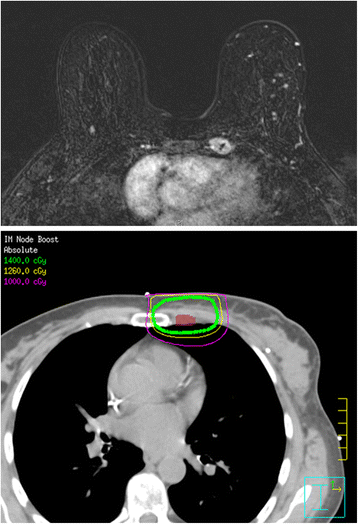

Background: The internal mammary (IM) lymph node chain, along with the axillary nodal basin, is a first-echelon breast lymphatic draining site. A growing body of evidence supports irradiation of this region in node-positive breast cancer. This study evaluated the effectiveness of radiotherapy in treating magnetic resonance imaging (MRI)-detected abnormal IM lymph nodes in newly-diagnosed non-metastatic breast cancer.

Results: Of the 7070 women who underwent pre-treatment MRI, 19 (0.3%) were identified on imaging to have a total of 25 abnormal pre-treatment IM lymph nodes, of which 96% were located in the first two intercostal spaces and 4% in the third space. A majority of the primary tumors were high-grade (94.7%) and hormone-receptor negative (73.7%), while 47.4% overexpressed HER-2/neu receptor. Axillary nodal disease was present in 89.5% of patients, while one patient had supraclavicular involvement. At a median follow-up of 38 months, 31.6% of patients had developed metastatic disease and 21.1% had died from their disease. Of the patients who received IM coverage, none had progressive disease within the IM lymph node chain.

Conclusions: Radiologic evidence of pre-treatment abnormal IM chain lymph nodes was associated with advanced stage, high grade, and negative estrogen receptor status. The majority of positive lymph nodes were located within the first two intercostal spaces, while none were below the third. Radiation of the IM chain in combination with modern systemic therapy was effective in achieving locoregional control without surgical resection in this cohort of patients.